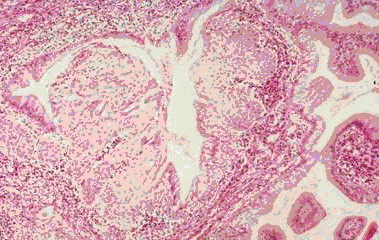

举例来说,慢性宫颈炎(宫颈糜烂)与宫颈癌在妇科阴道镜检查时观察到的表现可以相似。行宫颈刮片的细胞检查时看到的也可以相似(图1、2)。最后采取组织行病理切片检查,也是有相似之处,不是容易做出100%鉴别的(图3、4)。这样看来,如果仅一次检查(或一家医院检查),就肯定是癌,而行手术切除,是不慎重的,错误率是高的。最好是如果要手术切除,应到第二家医院或第二个医生核实后进行下一步治疗。

图3 宫颈炎看到的切片

图4 宫颈癌时看到的切片